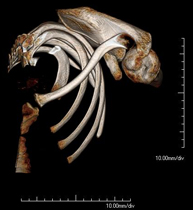

Exploració radiològica que mitjançant un sistema de raigs X i detectors que giren al voltant del pacient i que reconstrueixen les imatges per ordinador, permet l'estudi detallat de l'estern. - TC Clavícules

Exploració radiològica que mitjançant un sistema de raigs X i detectors que giren al voltant del pacient i que reconstrueixen les imatges per ordinador, permet l'estudi detallat de les clavícules. - TC Parrilla costal

Exploració radiològica que mitjançant un sistema de raigs X i detectors que giren al voltant del pacient i que reconstrueixen les imatges per ordinador, permet l'estudi detallat detalla de la Parrilla. - Angio- TC Cardíac o TC Cardíac

- TC d'espatlla

Exploració radiològica que mitjançant un sistema de raigs X i detectors que giren al voltant del pacient i que reconstrueixen les imatges per ordinador (TC Multidetector), permet l'estudi detallat dels ossos, els músculs i les articulacions de l'espatlla. - TC de colze